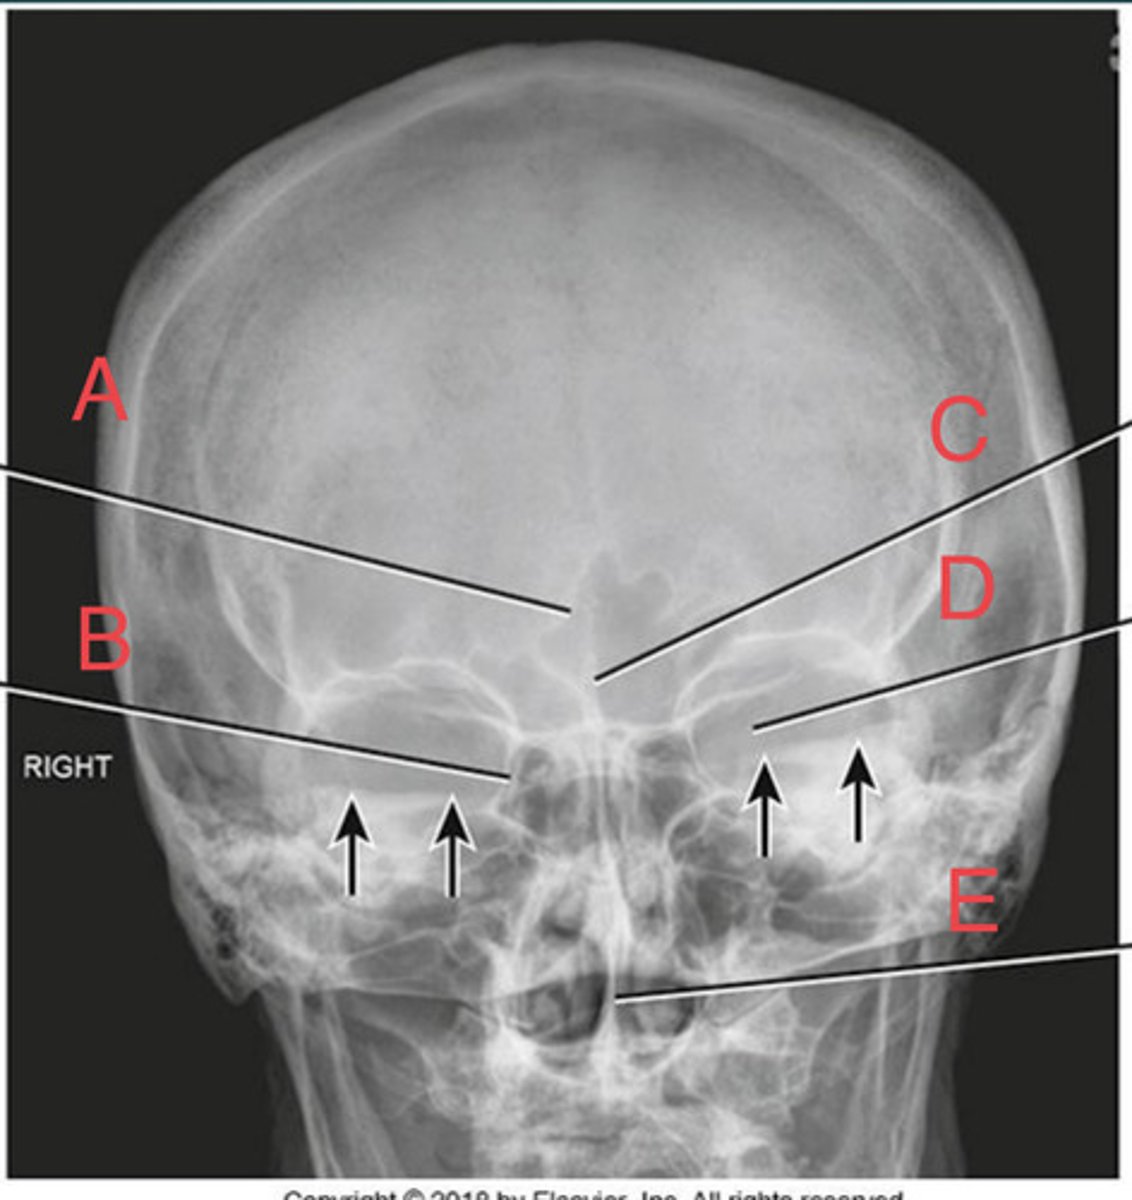

Waters sinus method

What projection?

r. frontal sinus of the frontal bone

A.

R. Maxillary sinus of maxilla

B.

R. petrous ridge of temporal bone

C.

bony nasal septum

D.

L. inferior orbital fissure of sphenoid bone

E.

Sphenoid sinus of sphenoid bone

F.

bony nasal septum

E.